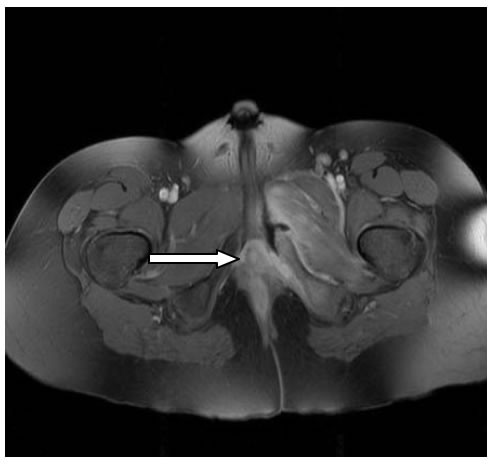

Decidiamo di eseguire la RMN del bacino. (Figura

1)

Tale indagine ci permette di evidenziare una localizzazione

ascessuale a carico dei muscoli otturatore interno ed esterno di sx

consensuale ad un quadro di osteomielite della branca ischio-pubica

di sx. Alla luce di tali evidenze ripetiamo, poi, una radiografia del

bacino (a distanza di circa 2 settimane dall'esordio della

sintomatologia) che effettivamente dimostra il rimaneggiamento

osteo-strutturale della branca ischio-pubica di sx. confermando,

pertanto, il limite “temporale” di tale metodica. (Figura

2)

Figura

1.

RMN: estesa alterazione di segnale coinvolgente la branca

ischio-pubica sx ed i muscoli otturatori omolaterali. La branca

ischiopubica mostra un'architettura spongiosa irregolare con

interruzione corticale sul margine anteriore; i gruppi muscolari

appaiono aumentati di volume e caratterizzati da segnale interno

disomogeneo con componenti liquide settate da riferire a raccolte

ascessuali.